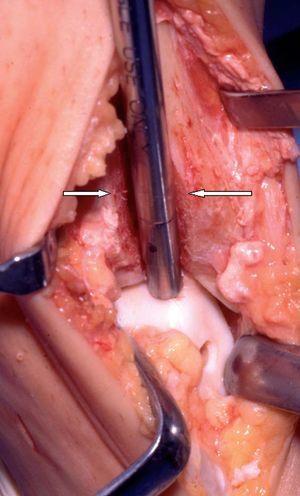

Figura 13

Inserción de un cilindro osteocondral dentro de la lesión tras retirar temporalmente un bloque de hueso. La lesión tiene 6 mm de diámetro y se ve al forzar la flexión plantar. El bloque de hueso mide 9 mm de ancho, 1,1 cm de profundidad, y aproximadamente 4 cm de altura (las superficies de osteotomía están marcadas con flechas blancas). La zona dadora del trasplante osteocondral se ve en la cara anteromedial del astrágalo.